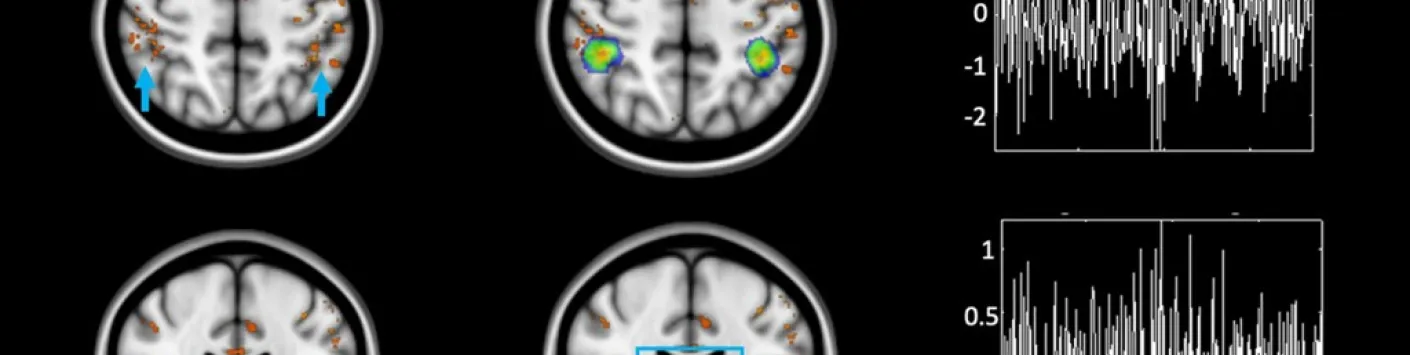

➡ L’équipe de chercheurs du GIGA-CRC-IVI, a à nouveau pu bénéficier de la plus grande résolution de l’IRM 7 Tesla pour montrer que le thalamus, une région sous-corticale située juste sous le corps calleux (qui relie nos deux hémisphères), joue un rôle de relais de l’information lumineuse non-visuelle vers le cortex pariétal dans une zone connue pour contrôler le niveau d’attention.